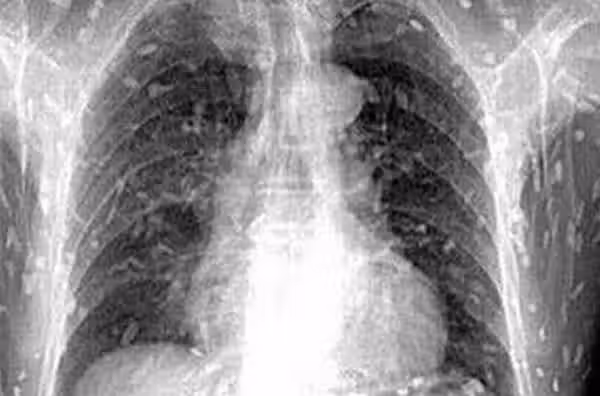

▲想 想 就 覺 得 可 怕!!!體內密密麻麻的寄生蟲!

2、感染寄生蟲

燒烤的東西外焦里嫩,有的肉裡面還沒有熟透,甚至還是生肉,有可能導致感染上寄生蟲,埋下了罹患腦囊蟲病的隱患。